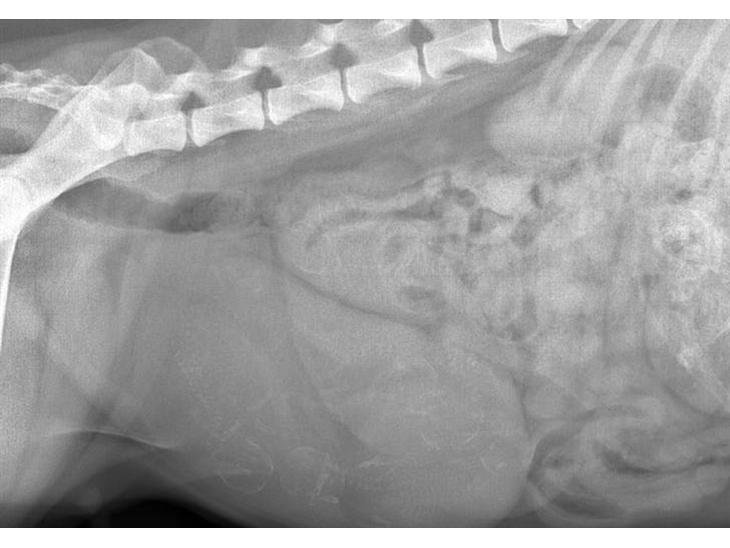

Her er røntgen billeder fra i dag. Dyrlægen lover, at der er fire men at der højst sandsynligt gemmer sig nogen flere "derinde" :D